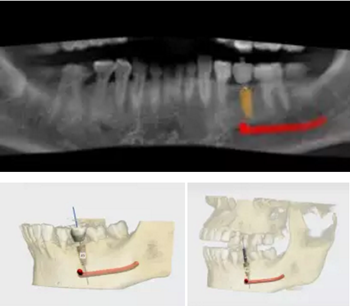

術(shù)前,導(dǎo)板設(shè)計(jì)工程師,根據(jù)CBCT以及模型數(shù)據(jù),將患者的解剖結(jié)構(gòu)、軟組織形態(tài)和修復(fù)效果數(shù)字化三維重建,在設(shè)計(jì)軟件內(nèi)進(jìn)行虛擬修復(fù)體冠設(shè)計(jì),同時(shí)與臨床醫(yī)生一起,根據(jù)#35牙槽骨高度以及寬度,結(jié)合下牙槽神經(jīng)管,設(shè)計(jì)好合適的種植位點(diǎn)。

根據(jù)上述植入和修復(fù)方案,立體設(shè)計(jì)Implant Guide™全程導(dǎo)板,鑒于下頜需避讓下頜神經(jīng)管,并考慮到種植體與頰舌側(cè)、近遠(yuǎn)中側(cè)的關(guān)系,設(shè)計(jì)在該牙位植入1顆Alpha-Bio Tec ICE 4.2x 10mm的植體。

術(shù)前術(shù)后CBCT數(shù)據(jù)對(duì)比分析,植體就位準(zhǔn)確。